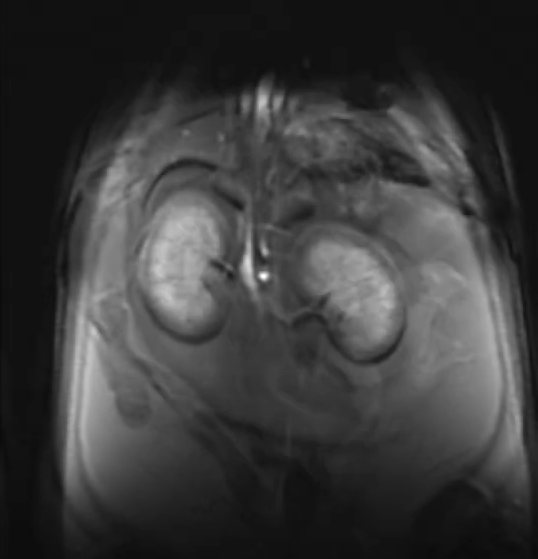

Examples of images acquired by our 7T MRI

MRI images of rat spine, brain tumor, fat imaging and mouse in-utero